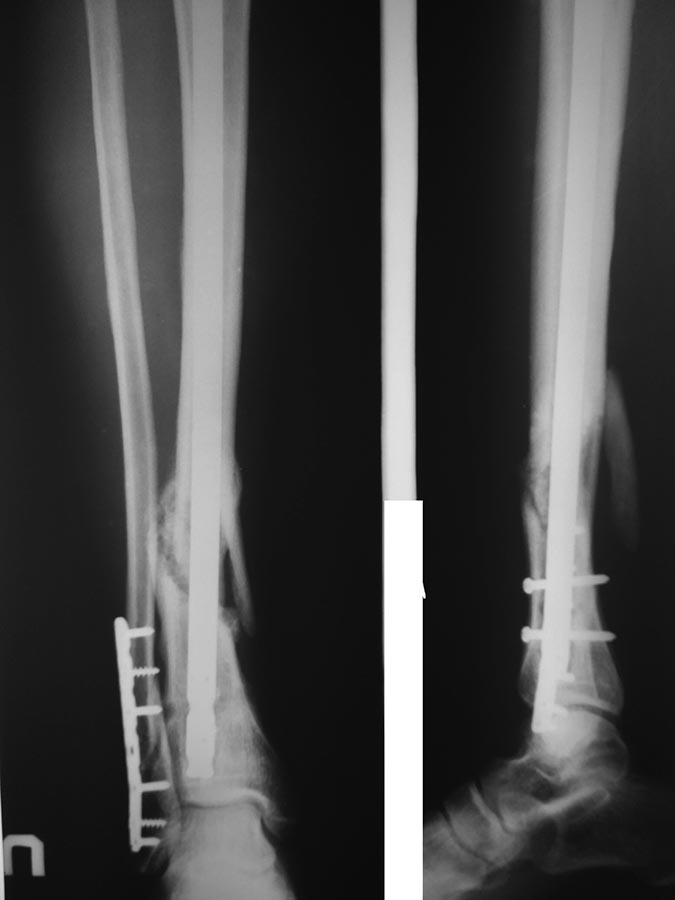

[Ortho] Замедленная консолидация ББК

снимок